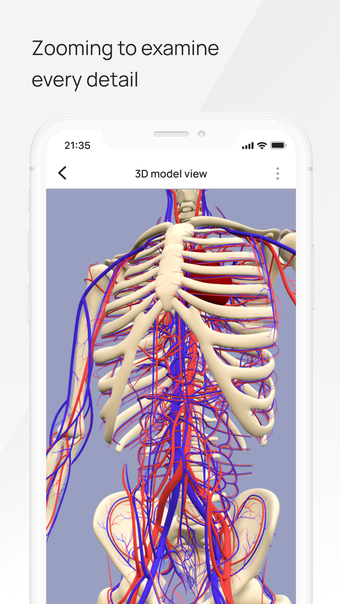

In this atlas of human pathologies you can learn about diseases, their causes, symptoms, and treatment. It contains all the essential information about the anatomy of the human body and its organs. You will be able to study diseases and their causes from an anatomy point of view. It contains information about diseases, their symptoms, and their treatment. In addition, you will be able to view 3D models of all the important organs of the human body.

All 3D pathology models are developed in close cooperation with medical experts of hospitals and research centers. They are thought out to the very smallest detail. Each category contains models of healthy organs.